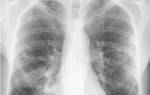

- Рентгенография является одним из наиболее информативных методов диагностики пневмонии. На рентгенограмме можно заметить зоны затемнения легочного рисунка, а в случае развития плеврита – уровень жидкости.

Диагностика стрептококковой пневмонии

Пульмонологи устанавливают диагноз стрептококковой пневмонии после осмотра пациента, изучения его медицинской истории, анализа результатов лабораторных и инструментальных исследований. Наиболее эффективным методом диагностики, который позволяет врачу определить наличие пневмонии и сделать выводы о характере возбудителя, является проведение рентгенографии в двух проекциях или крупнокадровой флюорографии.

При просмотре рентгенограммы лёгких, очаги воспаления выглядят как местное снижение воздушности легочной ткани различной степени плотности и распространённости. У пациентов с заболеванием стрептококковой пневмонией могут быть выявлены признаки очагового, ограниченного (полисегментарного), субтотального и тотального затемнения.

Признаки снижения воздушности связаны с проникновением ткани лёгких. При тяжёлом течении заболевания стрептококковой пневмонией происходит некроз ткани лёгкого, её разрушение, что на рентгеновском снимке выглядит как неравномерное проникновение с образованием плотных полостей.

Пневмония, вызванная пневмококком (стрептококком пневмонии), характеризуется следующими рентгенологическими признаками:

- небольшое затемнение в легочной ткани, обычно сопровождается небольшим воспалением;

- воспаление целой доли легких, часто с поражением плевры и скоплением жидкости в плевральной полости;

- ограниченное затемнение нескольких сегментов легочной доли.

При развитии воспалительного процесса в лёгких, вызванного пиогенным стрептококком, специалисты по рентгенологии Юсуповской больницы выявляют на рентгенограммах частичное или полное затемнение лёгких, наличие полости с жидкостью или без неё, увеличение толщины плевры и скопление жидкости в плевральной полости.

Если рентгенологические методы исследования не могут установить точный диагноз, врачи Юсуповской больницы проводят компьютерную томографию, которая помогает выявить инфильтрацию легочной ткани и увеличение лимфатических узлов корня лёгкого. Эта процедура используется для различения пневмонии от рака лёгкого или туберкулёза.